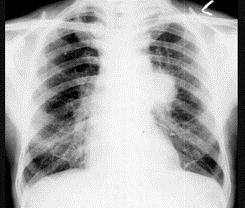

问题 60岁,男,有长期抽烟史,左声带麻痹、声音嘶哑2个月,请结合胸片和CT图.选出最可能的诊断 ( )

选项 A、肺炎 B、肺结节病 C、肺结核 D、尘肺 E、肺癌

答案 E